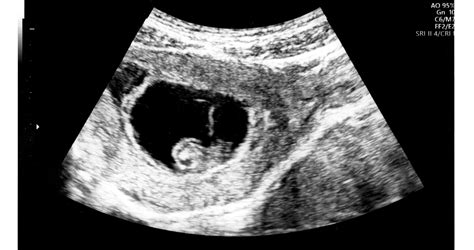

Várandósgondozás és ultrahang-diagnosztika

A várandósgondozás során a legfontosabb cél, hogy minden kismama biztonságban érezze magát a terhessége alatt.

A várandósgondozás során az alábbi ultrahang vizsgálatok érhetők el:

- Az első trimeszteri ultrahang (11-13. hét).

- A második trimeszteri, úgynevezett genetikai ultrahang (18-22. hét).

- A harmadik trimeszteri ultrahang (30-32. hét).